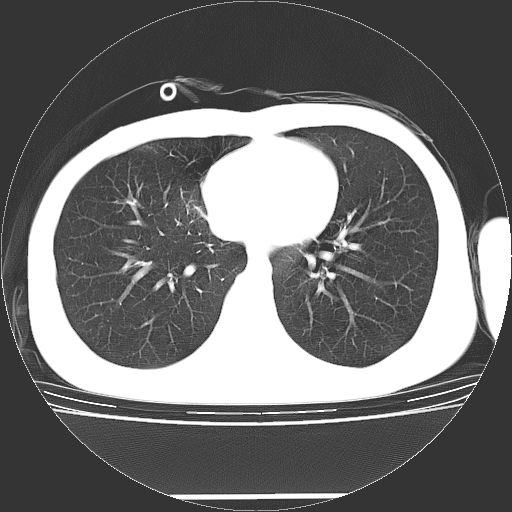

标题: CT19767:男,20岁,右侧气胸行闭式引流术后五天CT检查。 [打印本页]

标题: CT19767:男,20岁,右侧气胸行闭式引流术后五天CT检查。

男,20岁,右侧气胸行闭式引流术后五天ct检查看肺内是否有肺大泡,纵隔窗未见异常,未上传。

未见肺大泡影

右肺未见确切肺大泡。

1)右侧胸腔闭式引流术后导管留置。2)右肺未见肺大泡。

未见肺大泡,还有微量气体。